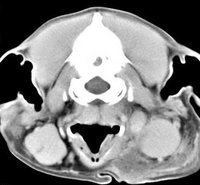

imágenes de TC en el perro | ||||||||||

ejemplo de imágenes de TC en el perro. Nótese la celulitis en la región parotídea izquierda | ||||||||||